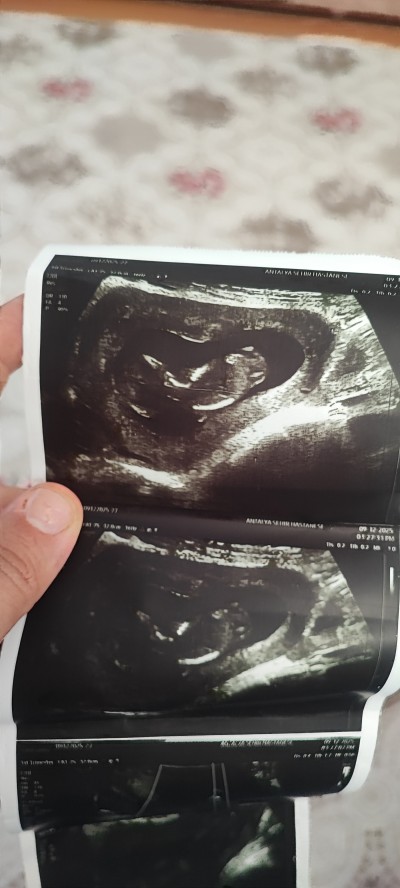

Kızlar merha nuba göre cinsiyet tahmini yapabilen varmı

image

Ben 13. Haftada yapay zekaya ultrason fotografini koyup nub teorisine göre cinsiyeti yorumlar misin yazdım doğru çıktı